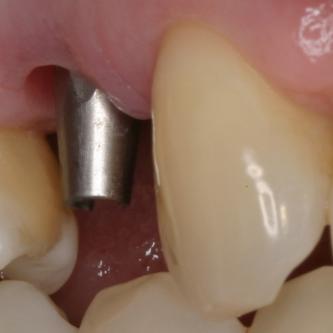

Exemple 3: Un implant à la place d'une incisive latérale supérieure droite. Sur cette image on voit le moignon en titane qui est vissé sur l'implant.

Exemple 3: Puis sur ce moignon, la couronne en céramique est scellée.